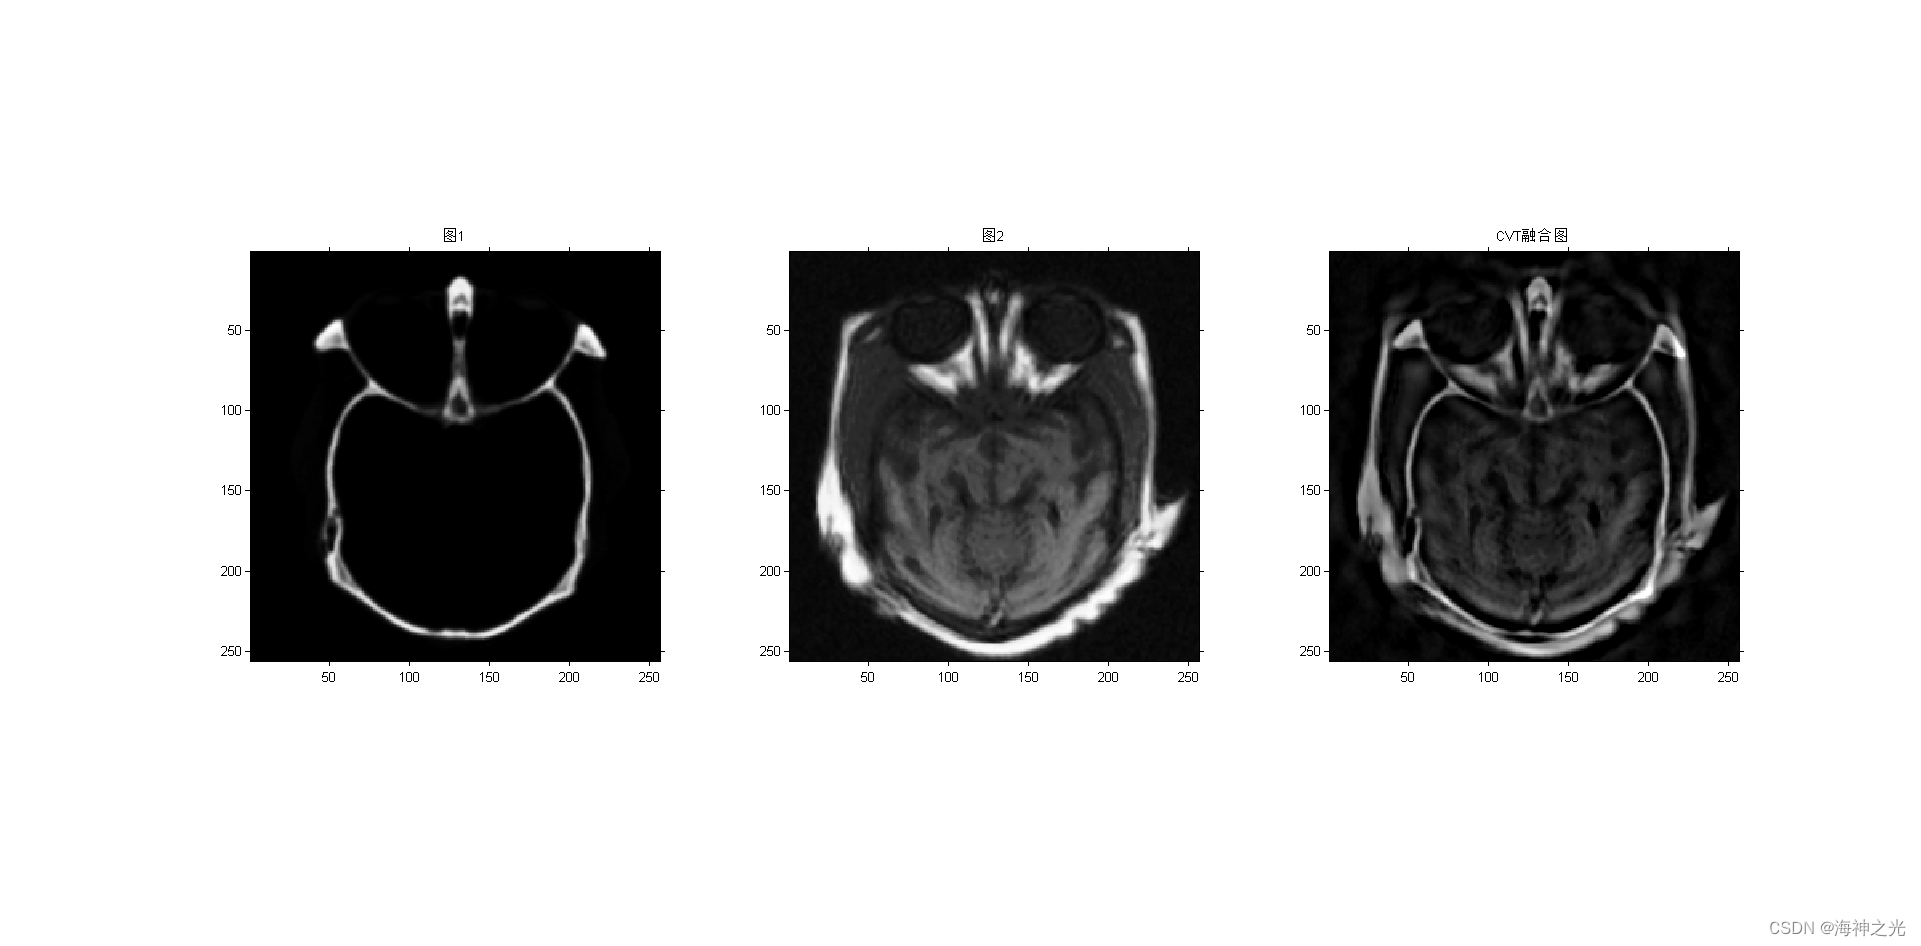

figure;subplot(131);imshow(image_input1);title(‘图1’)

subplot(132);imshow(image_input2);title(‘图2’)

F = curvelet_fuse(A,B,level+1); %CVT

title(‘CVT融合图’)